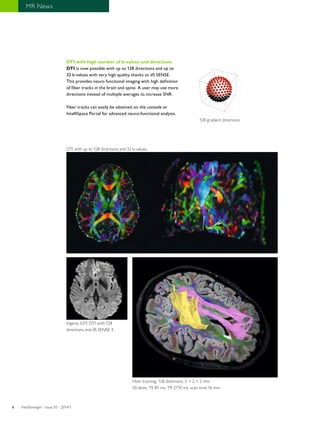

DTI with high number of b-values and directions

DTI is now possible with up to 128 directions and up to

32 b-values with very high quality thanks to dS SENSE.

This provides neuro functional imaging with high definition

of fiber tracks in the brain and spine. A user may use more

directions instead of multiple averages to increase SNR.

Fiber tracks can easily be obtained on the console or

IntelliSpace Portal for advanced neuro-functional analysis.

DTI with up to 128 directions and 32 b-values.

Ingenia 3.0T, DTI with 128

directions and dS SENSE 3.

128 gradient directions

Fiber tracking, 128 directions, 2 × 2 × 2 mm.

50 slices, TE 81 ms, TR 2710 ms, scan time 16 min.